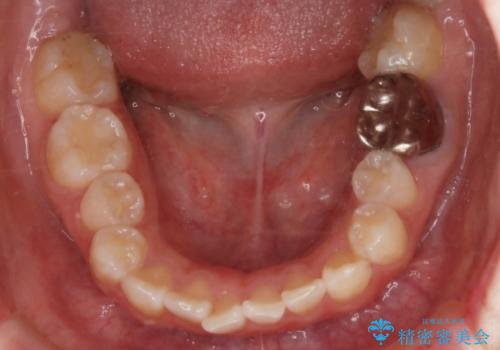

ハーフリンガル装置

ワイヤー矯正の中でも、上顎を裏側・下顎を表側に装置をつけて動かす方法をハーフリンガルといいます。

ハーフリンガルを選択すると、ワイヤー矯正の利点である抜歯ケースへの対応が可能な点と、表側の装置の欠点である装置が目立つという点をカバーして矯正治療を進めることができます。

表側の装置と違い、使えるワイヤーの種類に制限があり平均治療期間が長くなりやすい点、装置の作製自体の金額が掛かることから費用面で表側装置よりも高額になるという点はマイナスポイントであるといえますが、しっかりと口元を下げたり、噛み合わせの構築を行うことは遜色なく行えるため人気のある装置となっております。